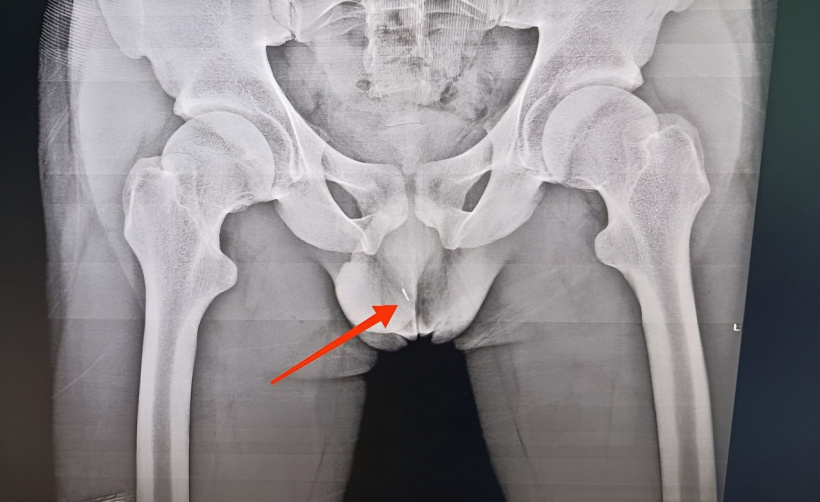

На снимке в области правой половины мошонки визуализируется игла (это оказалась английская булавка с отломанной головкой), - рассказывает врач-уролог Федор Михайлович Бабенко. - Оперативным путем под рентгенконтролем инородное тело удалено, через несколько дней пациент выписан».